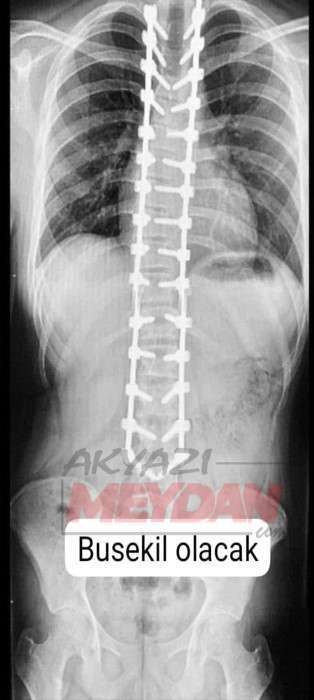

Skolyoz hastası Ecrin Selim'in ameliyatı için gerekli olan 125 bin lira için ailesi hayırsevelerden yardım çağrısında bulundu.

Skolyoz hastası (omurga eğriliği) Ecrin Selim, ameliyatla sağlığına kavuşacak. İstanbul'daki özel bir hastanede gerçekleştirilecek olan ameliyat için tetkikler, operasyonda kullanılacak implantlar ve ameliyat sonrası hastane bakımı giderleri olarak 125 bin liraya ihtiyaç duyuluyor.   Ameliyat masraflarını karşılayamayacak olan aile, hayırseverlerden çocuklarının tedavisi için yardım istedi.   İletişim : Babası Yakup Selim  0 541 842 70 54   TR33 0001 0023 5349 1257 7150 02